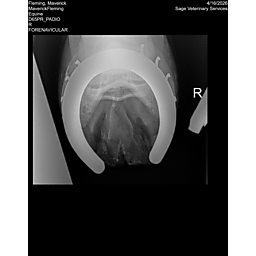

**Maverick sells at the Colorado Horse Sale’s Best of the West Select Sale on May 30th in Castle Rock, CO - He will complete the riding & handling Sift Exam, baseline veterinary exam, and will sell with 4 total radiographs (DLPMO & Front Foot Lateral)**